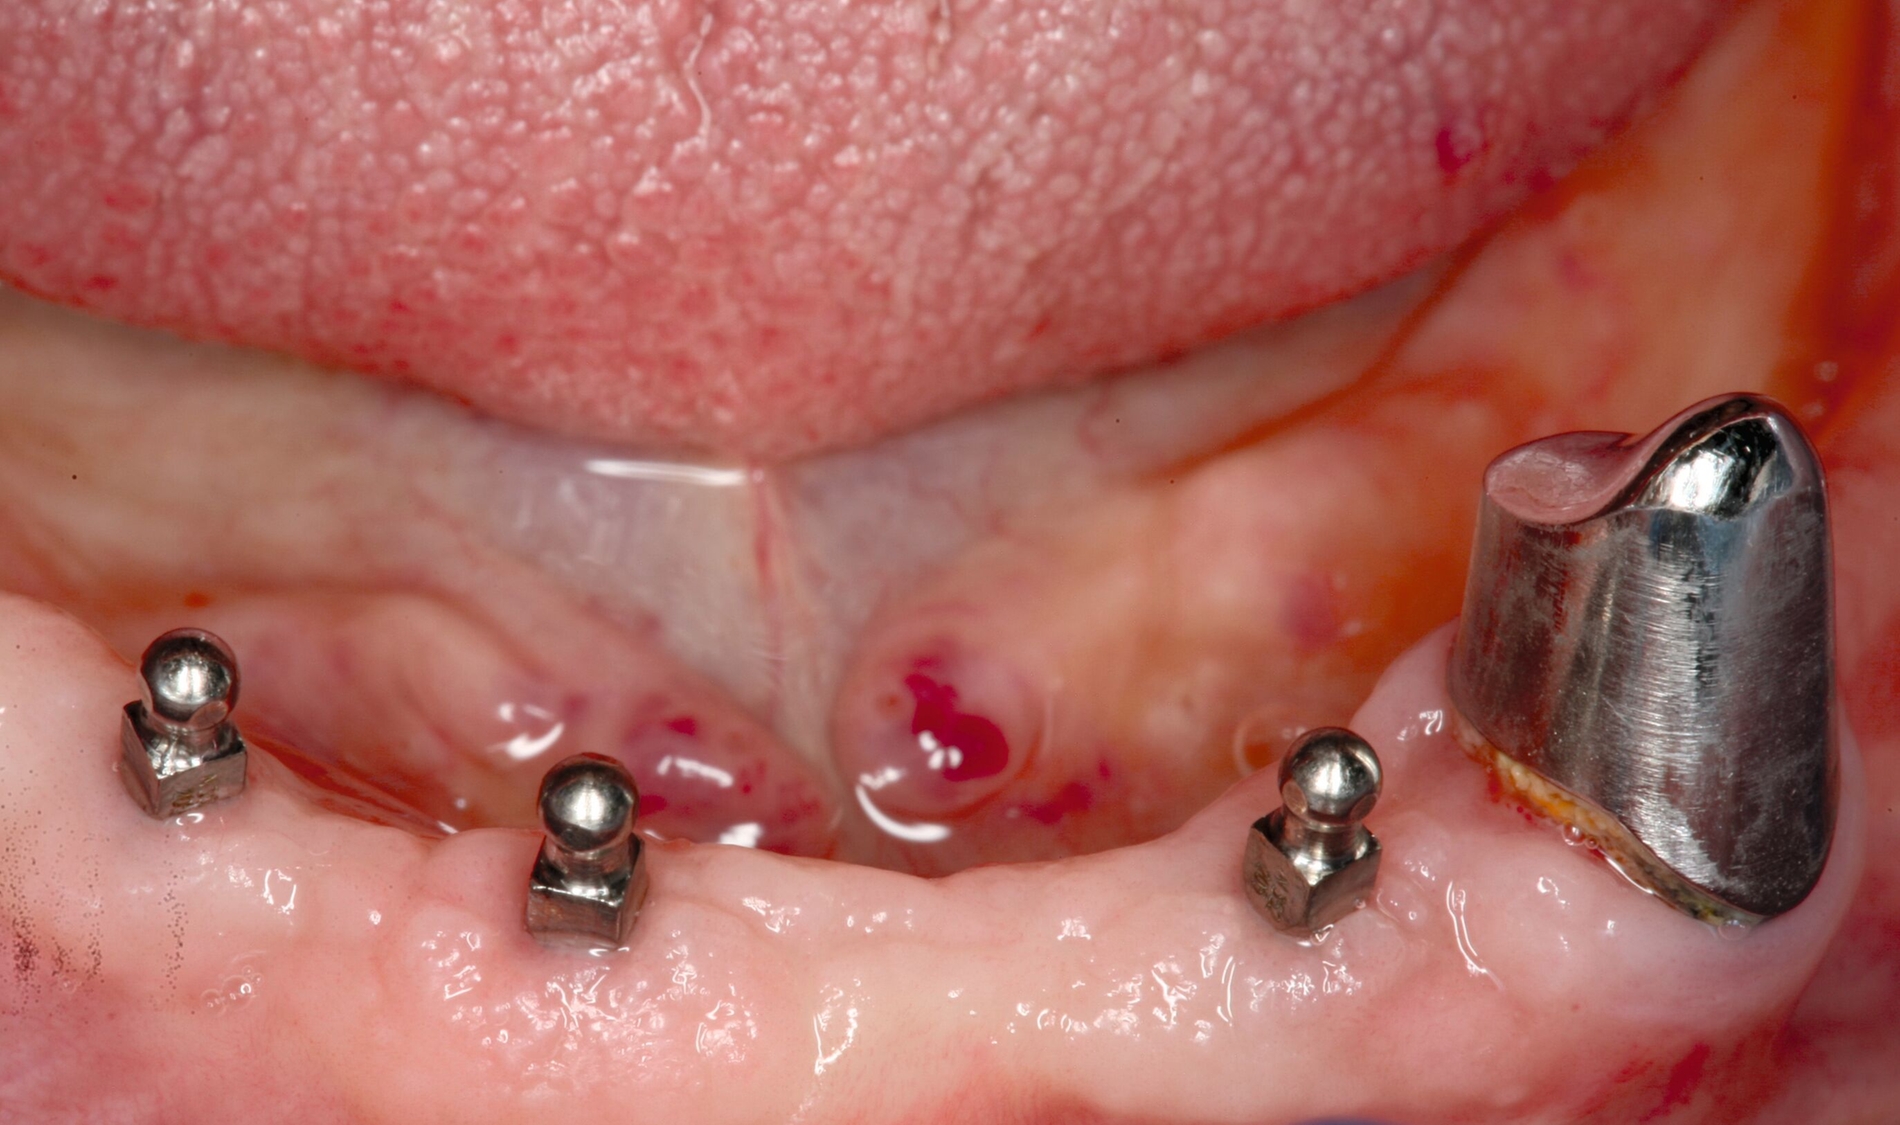

Zur Prothesenstabilisierung werden seit Ende der 1990er-Jahre Miniimplantate mit einem Durchmesser von weniger als 3 mm verwendet. Empfohlen werden hierfür vier interforaminale Implantate im Unterkiefer und sechs Implantate zwischen den Sinus maxillares im Oberkiefer (Abbildung 4) [Lemos et al., 2017]. In der Regel liegt der Implantat-Durchmesser zwischen 1,8 und 2,5 mm [Schiegnitz und Al-Nawas, 2018]. Sie sind deshalb bis auf wenige Ausnahmen [Morneburg und Proschel, 2008] einteilig [Jawad und Clarke, 2019]. Eine vollkommen belastungsfreie Einheilung ist deshalb nicht möglich [Mundt et al., 2015]. Sie eignen sich für sehr schmale Kieferkämme, bei denen anderenfalls Augmentationen notwendig gewesen wären. Viele Anwender inserieren Miniimplantate erfolgreich transgingival („flapless“) [Marcello-Machado et al., 2018]. Der Autor dieses Beitrags empfiehlt jedoch sicherheitshalber die Bildung eines kleinen Mukoperiostlappens zur Kontrolle der Insertionsstelle („mini-flap“) und die transgingivale Insertion nur bei breiten Kieferkämmen oder nach dreidimensionaler Bildgebung zusammen mit einer Bohrschablone für eine geführte Aufbereitung.

Mittlerweile gibt es zahlreiche Hersteller, die Miniimplantate in ihr Produktportfolio aufgenommen haben. Am häufigsten werden Kugelköpfe zur Verankerung auf Miniimplantaten genutzt [Marcello-Machado et al., 2018], aber es gibt dafür auch eine Reihe anderer Patrizen- und Matrizenformen wie Magnete, Locatoren oder ähnliche Verankerungen und sogar Stege [Leles et al., 2022; Lemos et al., 2017]. Beispielhaft zeigt die Abbildung 5 eines der ersten Miniimplantat-Systeme, dass inzwischen in zahlreichen Studien überprüft wurde [Enkling et al., 2019, Lemos et al., 2017, Shatkin und Petrotto, 2012]. Die Länge beginnt bei 10 mm, hauptsächlich werden jedoch 13 mm lange, 1,8-mm-Miniimplantate im Unterkiefer und 2,4-mm-Miniimplantate im Oberkiefer verwendet. Die Aufbereitungstiefe mit dem dünneren 1,1-mm-Bohrer richtet sich nach der Knochenqualität. Durch das selbstschneidende Gewinde erlangt das Implantat ähnlich einer Holzschraube seine primäre Stabilität. Erst bei einem finalen Eindrehmoment ab 35 Ncm aller Implantate pro Kiefer sollte eine Sofortbelastung erfolgen. Dafür werden die Matrizen (Housing mit einem O-Ring aus Nitrilgummi) entweder intraoral oder über eine Abformung in die Prothese einpolymerisiert. Ist das Eindrehmoment geringer, sollte die Prothese zunächst für drei Monate weichbleibend unterfüttert werden [Mundt et al., 2015]. Die Kugel nutzt seitlich nicht ab, da der O-Ring bei der Protheseneingliederung über den Äquator gleitet und darunter auf dem Insertionsvierkant verbleibt. Die Haftkraft ändert sich auch nach Jahren nicht, wenn der O-Ring bei Abnutzung ausgetauscht wird [Abou-Ayash et al., 2019].